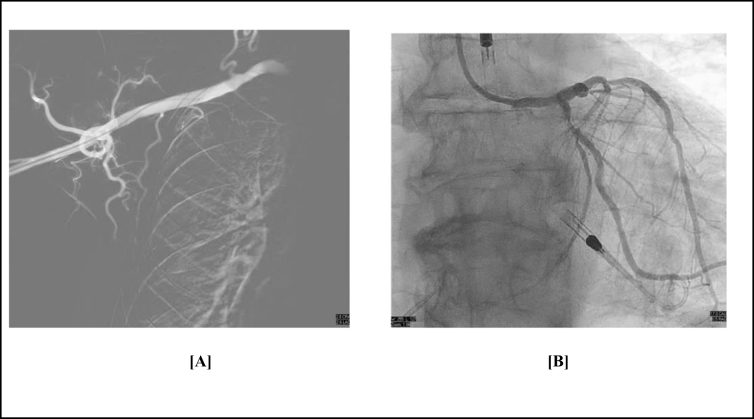

Case presentation: We present the case of a 68-year-old male with severe multivessel coronary artery disease with reduced left ventricular ejection fraction, and bilateral iliofemoral artery disease. Since there was difficulty in accessing the femoral arteries, axillary artery access was used to insert an Impella CP device to support high-risk PCI. The procedure involved successful revascularization of complex lesions using rotational atherectomy and stenting. The patient remained hemodynamically stable throughout and recovered without complications.